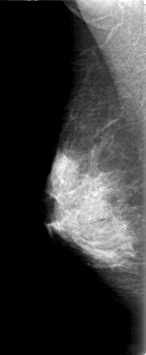

D_4168_1.RIGHT_MLO

DATE_OF_STUDY 9 11 1998

PATIENT_AGE 48

DENSITY 3

RIGHT_MLO LINES 5311 PIXELS_PER_LINE 2176 BITS_PER_PIXEL 12 RESOLUTION 43.5 NON_OVERLAY